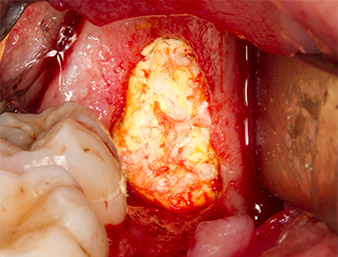

The tissue above the root remnant was not completely ossified and consisted for the most part of granulation tissue modified by inflammation (Fig.4).

To obtain autogenous material for subsequent wound treatment, healthy bone chips were harvested from the surroundings of the root remnant with a piezo surgical instrument (Piezomed B5) (Fig. 5).

The autogenous tissue was removed with the scraper-shaped section of the working part of the instrument and stored in a physiological saline solution until further use (cf. Fig. 13).